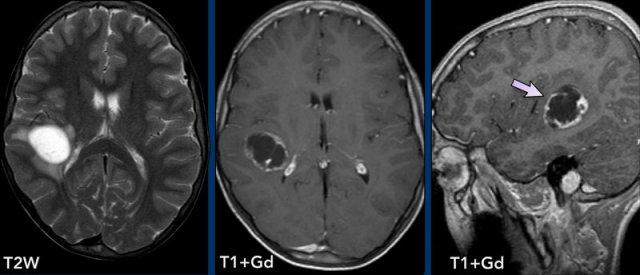

Các hình ảnh này của một phụ nữ 76 tuổi, có biểu hiện lú lẫn sau khi ngã.

Hãy quan sát các hình ảnh trước rồi mới tiếp tục đọc.

Câu hỏi:

- Chẩn đoán có khả năng nhất là gì?

- Những dấu hiệu nào điển hình cho chẩn đoán này?

Các dấu hiệu bao gồm:

- Tổn thương tăng tỷ trọng trên CT không tiêm thuốc cản quang kèm phù não do mạch máu.

- MRI cho thấy nhiều tổn thương ngấm thuốc dạng đặc và hạn chế khuếch tán.

- Trên chuỗi xung T2W, các tổn thương biểu hiện giảm tín hiệu.

- Một tổn thương nằm ở thể chai và một tổn thương khác nằm cạnh não thất.

Tất cả các dấu hiệu này đều điển hình cho u lympho nguyên phát hệ thần kinh trung ương, khác với u lympho hệ thống.

Các khối u này chiếm 6-7% tổng số u hệ thần kinh trung ương và mô học là u lympho tế bào B không Hodgkin.

Chúng thường nằm ở vùng cạnh não thất dưới màng nội tủy, thể chai và hạch nền.

Luôn nghĩ đến u lympho khi gặp tổn thương ngấm thuốc dạng đặc nằm gần não thất.

Hình ảnh tăng tỷ trọng trên CT, giảm tín hiệu nhẹ trên chuỗi xung T2W cũng như hạn chế khuếch tán được giải thích là do mật độ tế bào dày đặc của mô u lympho.

Ở bệnh nhân suy giảm miễn dịch, kiểu ngấm thuốc có thể là dạng vòng nhẫn.

Bệnh nhân này có nhiều phù não, nhưng trong nhiều trường hợp phù não rất hạn chế.